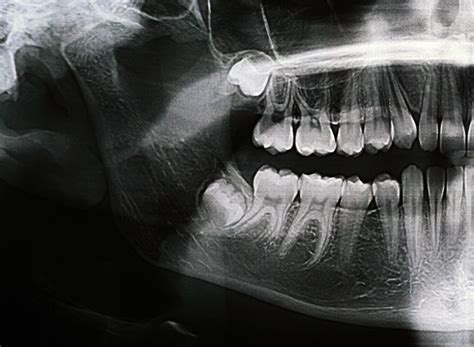

Once you suspect that your wisdom teeth are causing issues, a professional evaluation is non-negotiable. Dentists typically use panoramic X-rays to view the orientation and proximity of the teeth to your nerves and sinuses. If the teeth are impacted or causing damage to neighboring structures, extraction is usually the recommended course of action.